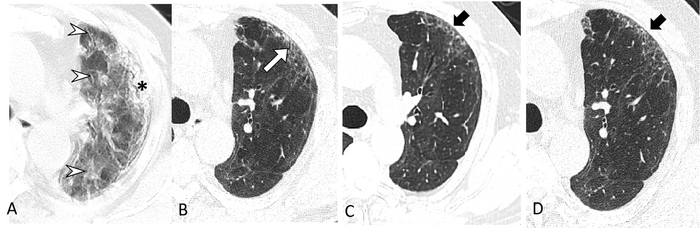

Residual lung abnormalities after discharge from the hospital included fibrosis (scarring), thickening, honeycombing, cystic changes, dilation of the bronchi, and more.

Over two years, the incidence of lung abnormalities gradually decreased. At six months, 54% of patients showed lung abnormalities. On two-year follow-up CT scans, 39% (56/144) of the patients had lung abnormalities, including 23% (33/144) with fibrotic lung abnormalities and 16% (23/144) with non-fibrotic lung abnormalities.

“In particular, the proportion of fibrotic interstitial lung abnormalities, an important precursor to idiopathic pulmonary fibrosis, remained stable throughout follow-up,” the authors said. “Therefore, the fibrotic abnormalities observed in our study might represent a stable, irreversible pulmonary condition, such as lung fibrosis, after COVID-19.”

“Long-term and functional consequences of chest CT findings post-COVID-19 are largely unknown,” the authors said. “Our prospective study found that 39% of participants had persistent interstitial lung abnormalities at two-year follow-up, which were associated with respiratory symptoms and decreased diffusion function.”